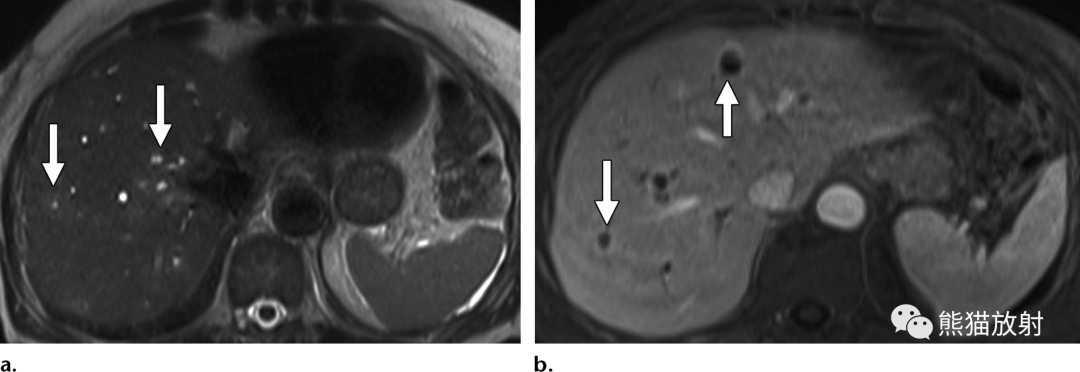

65岁男性,因急性坏疽性胆囊炎发生化脓性肝脓肿。(a)轴位T2WI显示脓肿壁的双靶征,表现为围绕脓肿内部高信号内容物的等低信号内层(箭头)和中等高信号外层(箭)。注意胆囊颈部嵌顿的低信号结石 (*)。(b)轴位对比增强动脉期脂肪抑制T1WI图像显示内层早期强化(箭头)和邻近节段性肝实质充血。(c)轴位对比增强延迟期图像显示内层和外层延迟强化(箭)。